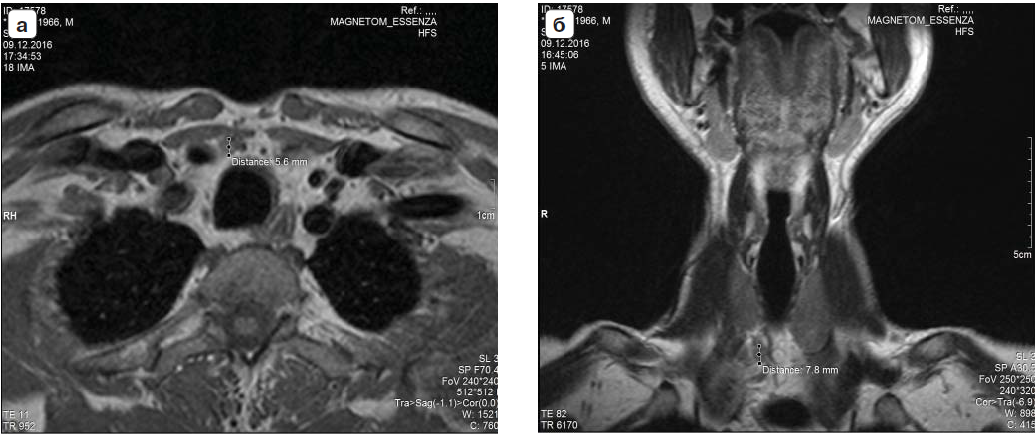

В 4 случаях была обнаружена эктопия ОЩЖ в верхнее средостение только благодаря МРТ, что не отмечалось ни по данным УЗИ-протокола, ни по данным сцинтиграфии. У 2 пациентов после проведения УЗИ, сцинтиграфии и компьютерной томографии убедительных данных за наличие патологии ОЩЖ не выявлено ввиду маленьких их размеров (размеры ОЩЖ не соответствовали уровню ПТГ). После проведения МРТ и применения программы подавления МР-сигнала от жировой ткани (STIR) было выявлено изменение МР-сигнала от патологически измененной ОЩЖ (рис. 2).

Рис. 2. Аденомы ОЩЖ, выявленные при МРТ-исследовании: а – на уровне нижнего полюса правой доли щитовидной железы, Th1, визуализируется образование округлой формы, с четкими ровными контурами, гипоинтенсивного МР-сигнала на Т1 ВИ, размерами 5,6 мм в аксиальной проекции; б – на уровне нижнего полюса правой доли щитовидной железы, Th1, визуализируется образование округлой формы, с четкими ровными контурами, гипоинтенсивного МР-сигнала на Т1 ВИ, размерами 7,8 мм в коронарной проекции.